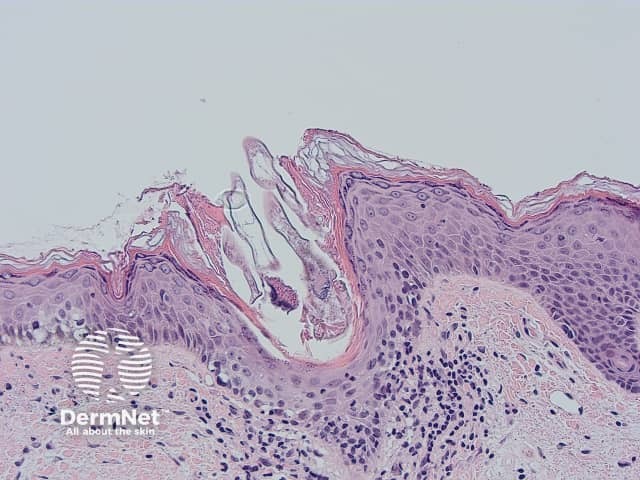

Demodex mite histology x200

Demodex may be found in mineral oil skin scrapings from the face by KOH examination, or in hair follicles in a skin biopsy examined under the microscope. The superficial part of the horny layer of the skin and the follicular content can also be sampled by skin surface biopsy. Demodicosis is diagnosed when there is a high density of demodex mites (> 5/cm2).

Demodex folliculorum is characterised histologically by: